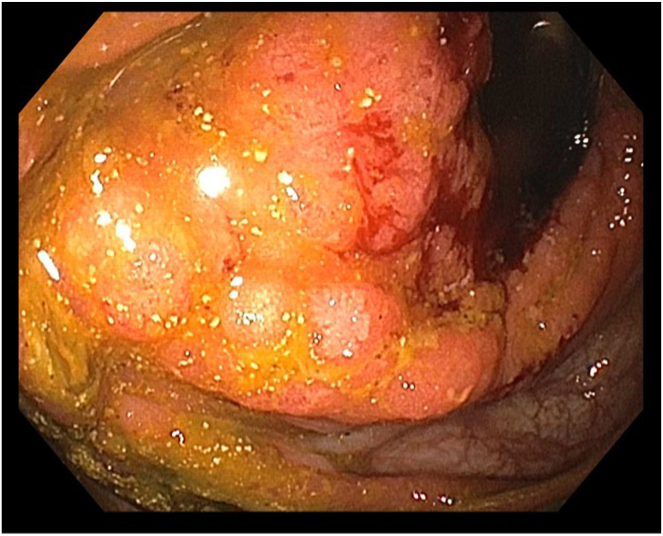

Malignant bowel obstruction is a challenging complication in advanced gastrointestinal malignancies with varying treatment strategies including medical, surgical and endoscopic therapies, each with their own limitations. Endoscopic ultrasound–guided enterocolostomy has been previously reported as an option for patients who are not surgical candidates or ideal candidates for enteral stenting. In this case, endoscopic ultrasound–guided enterocolostomy is used for the palliation in a patient with a completely obstructing large cecal adenocarcinoma who declined surgical intervention.